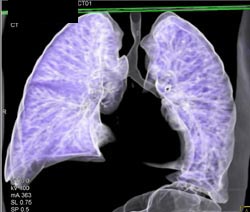

Airway Narrowing Due to Double Arch